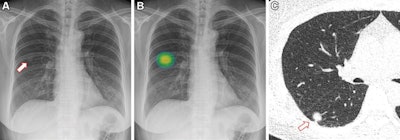

The researchers enrolled 10,476 adult participants who underwent at least one chest x-ray as part of a routine checkup at their hospital's health screening center between July 2020 and December 2021. Half of the images (5,238) were automatically assessed by the Insight CXR algorithm (Lunit) for the possibility of major thoracic abnormalities (pulmonary nodule, pneumonia, and pneumothorax) on a percentage scale from 0% to 100%. During image processing, the suspicious nodules were localized on the images with overlaid heat maps. The other half of the images served as controls.

One of three radiologists with 13 to 36 years of experience interpreted each radiograph for actionable nodules with and without the AI-based CAD results. Actionable nodules were defined as solid nodules larger than eight millimeters or subsolid nodules with a solid portion larger than 6 millimeters (Lung-RADS, category 4).